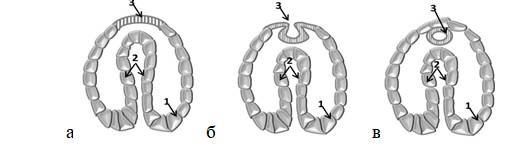

На 5-й неделе происходит закладка нервной системы зародыша – нейруляция (рис. 2). При этом из внешнего листка начинает формироваться нервная пластина. Она недолго остается уплощенной.

Рисунок 2. Нейруляция: формирование нервной трубки (3), эктодерма (1), эндодерма (2)

Вскоре ее боковые края приподнимаются, образуя нервные валики, края которых смыкаются, формируя замкнутую нервную трубку с каналом внутри. Сначала смыкание нервных валиков происходит на уровне шеи плода, а затем распространяется в головном и хвостовом направлениях. Примерно к 25-28 дню жизни эмбриона эта трубка полностью закрывается. Открытыми остаются лишь отверстия на ее концах.

Основная роль в формировании нервной трубки отводится фолиевой кислоте. Ее дефицит вызывает пороки развития. К моменту начала нейруляции должен присутствовать определенный запас витамина В9.